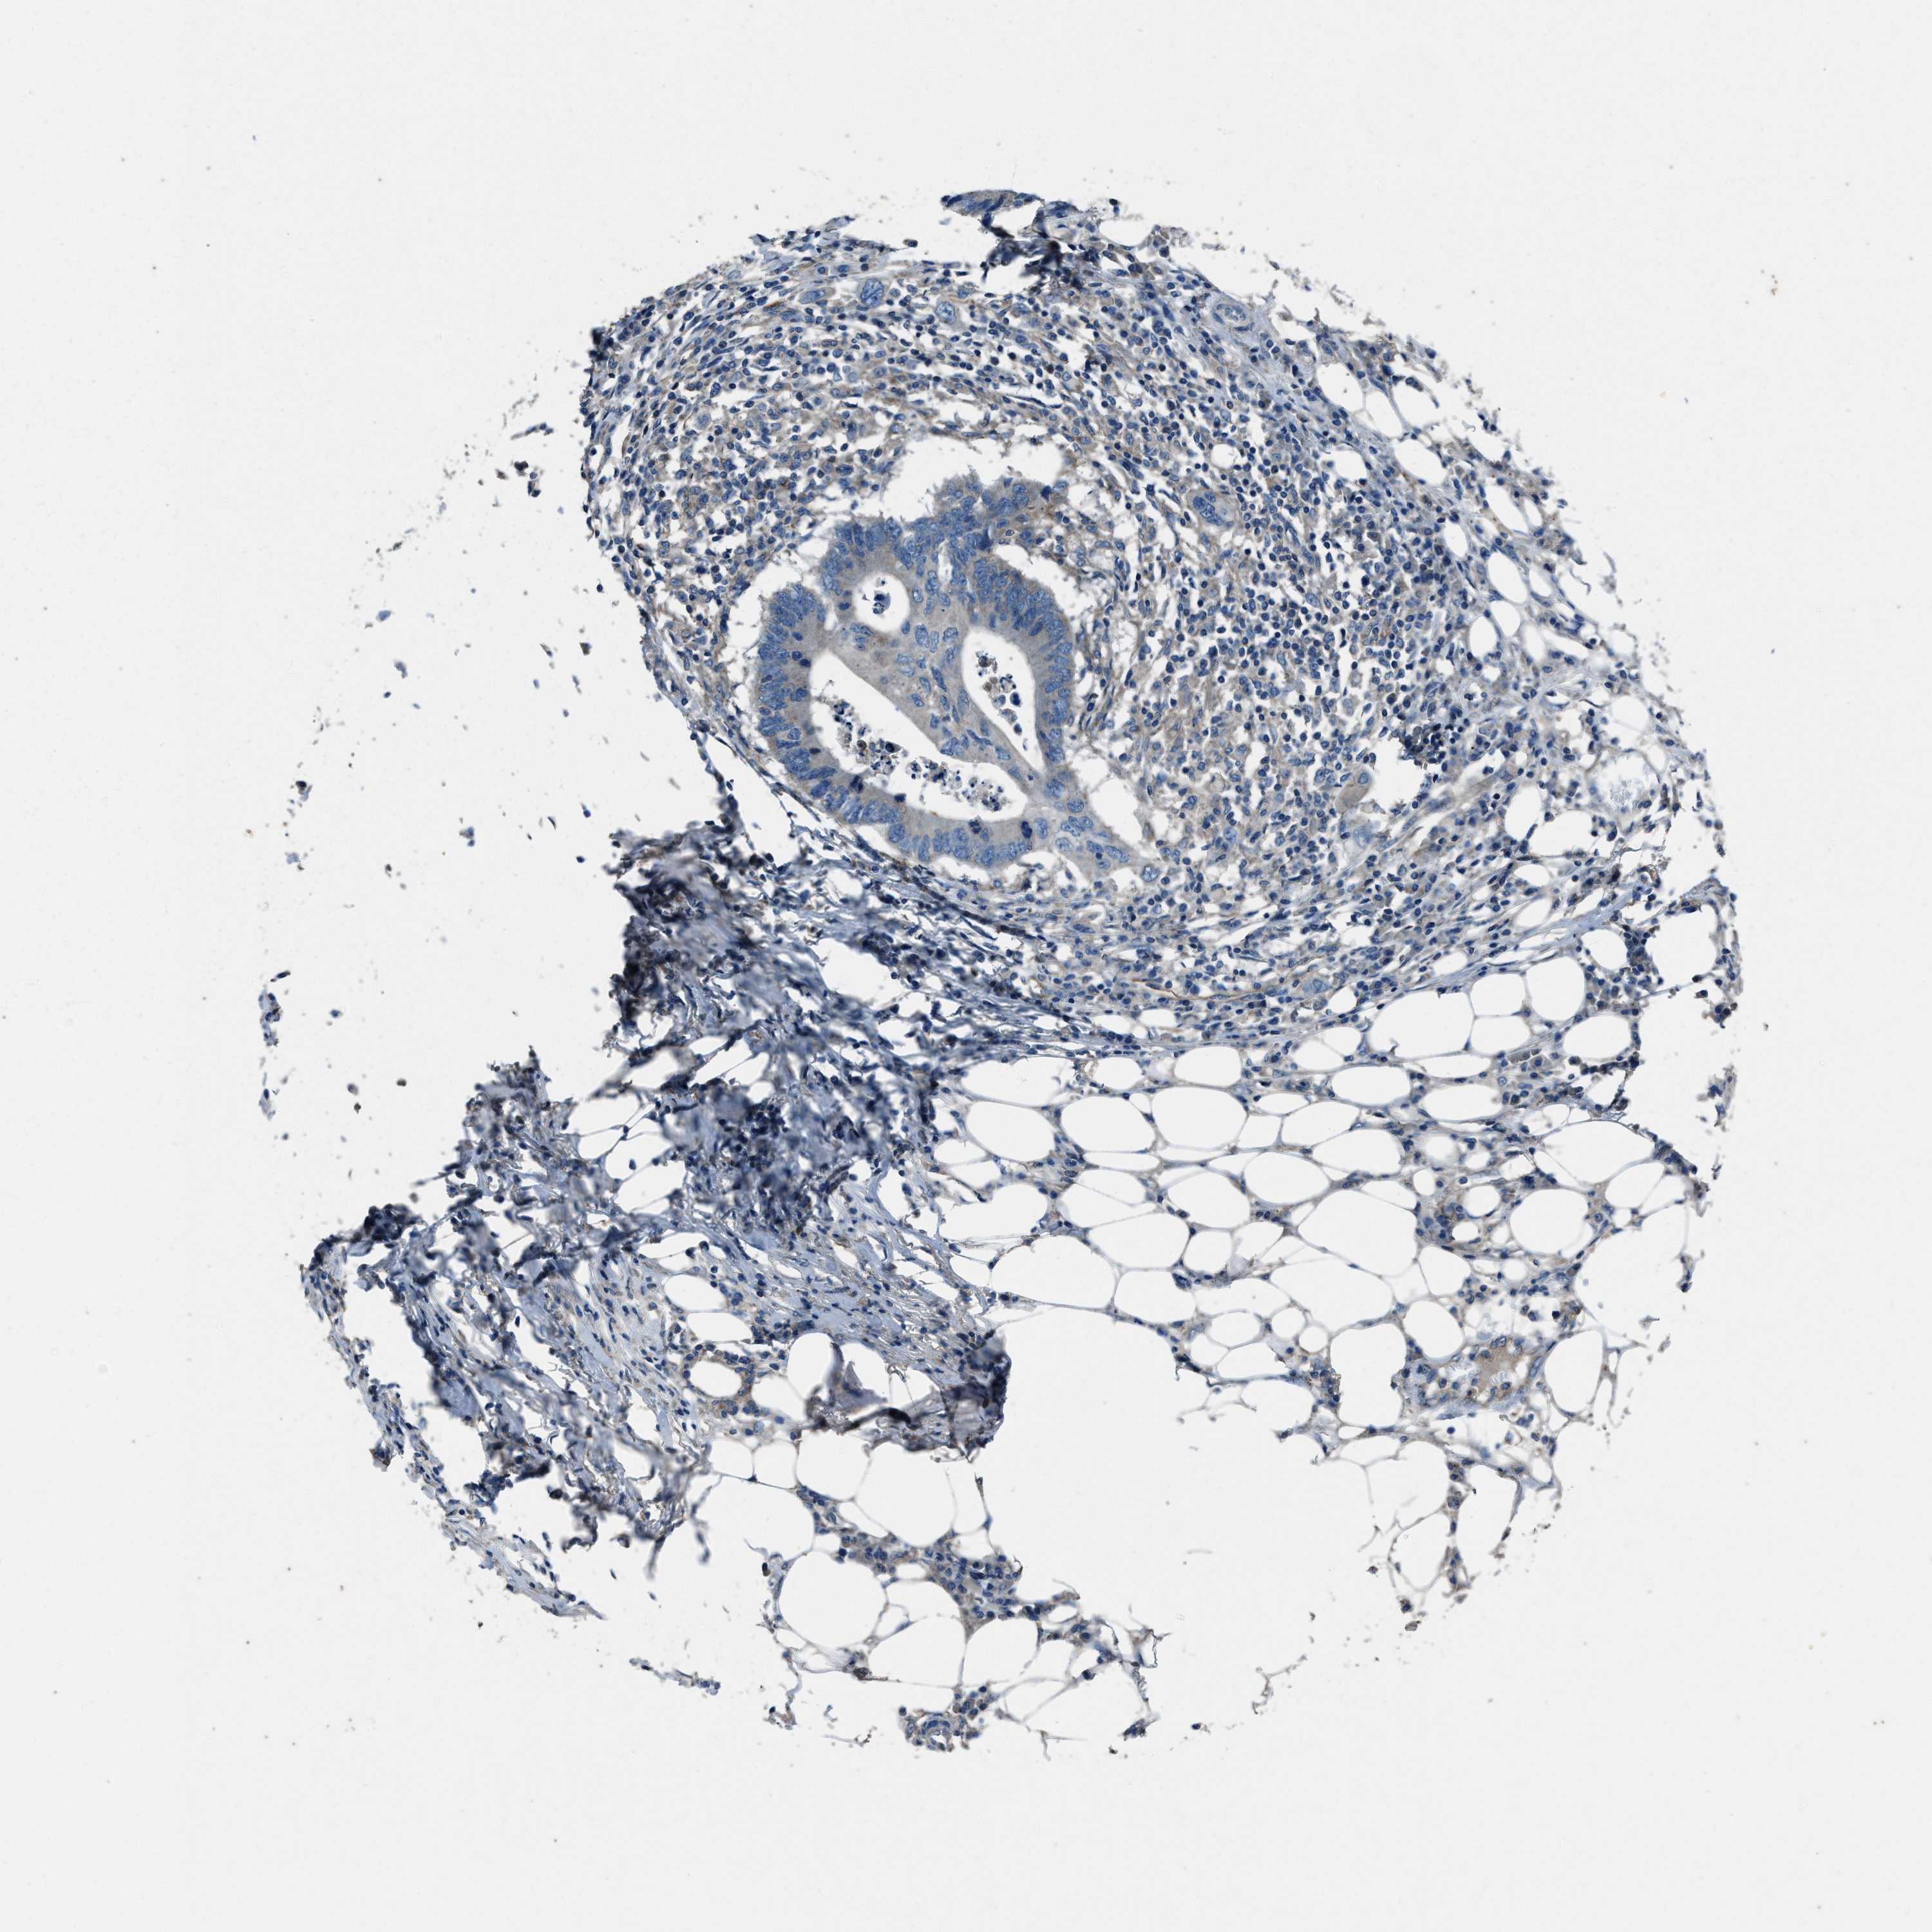

CANCER COLORECTAL CANCER Show tissue menu

Colorectal cancer

Human cancer

Colon adenocarcinoma